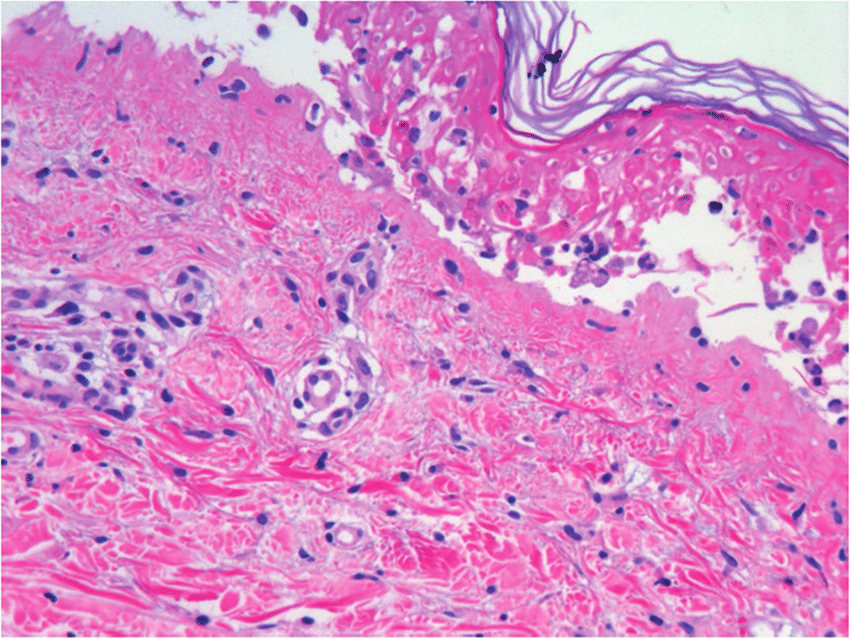

Necrólisis Epidérmica Tóxica: Revisión Clínica y Terapéutica

07 diciembre 2022

En general, su etiología y presentación son consensuadas, definiéndose como una necrólisis generalizada de la epidermis que se produce como una respuesta inmune descontrolada a un fármaco específico o a uno de sus metabolitos, destacando el cotrimoxazol y el alopurinol como los más importantes. Esta necrólisis conduce a un desprendimiento masivo de la capa epidérmica de la piel, con mayor incidencia en el torso, miembros superiores y cara. Eur. Burn J. 8 agosto 2022